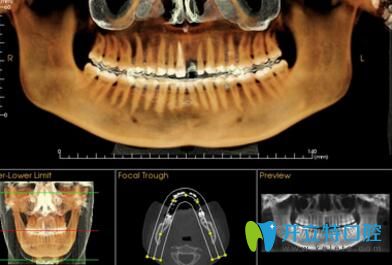

? 2、專業(yè)軟件分析:

? 一次3D掃描即可獲取全部原始記錄。在正畸治療計(jì)劃制定過程中為您創(chuàng)建全景片圖像、頭顱側(cè)位片圖像等所需影像。創(chuàng)建氣道分析所需的特定影像以及TMJ分析的校正圖像。利用可調(diào)節(jié)的失狀面視圖和立體透視功能,可以確定阻生和埋伏牙的位置。

長(zhǎng)沙美萊口腔數(shù)字化矯正專業(yè)軟件分析